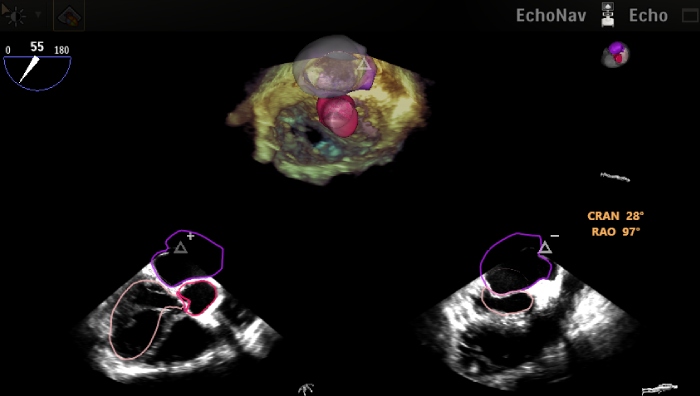

La fusion présente de grands avantages. Quel est votre regard sur un outil comme EchoNavigator ? Pour un meilleur dialogue, une meilleure communication avec les interventionnels, la fusion est un atout incontestable pour aider à guider un certain nombre de gestes pour lesquels la scopie, le retour radiographique est extrêmement important. L’association des 2 images – l’image radiographique sur l’image à rayon-x – va permettre à l’interventionnel de retrouver en partie ses standards de référence et l’apport écho cardiographique va lui permettre d’aller plus loin dans la manipulation des outils interventionnels. Dr Leroux : Il est évident que la fusion a plusieurs avantages. Le 1er, c’est la sécurité. Quand nous voyons vraiment en 3D les 4 cavités cardiaques et que nous avons, par exemple avec les corrections bord-à-bord Mitrale, besoin de naviguer dans l’oreillette gauche pour s’orienter vers la valve mitrale, le fait de voir les structures comme si nous y étions, augmente indéniablement la sécurité et à fortiori la rapidité d’action du geste. A cela s’ajoute un intérêt majeur en termes de formation. Pr Lafitte : La dernière chose est l’importance de cette fusion pour orienter au mieux l’arceau du Flexarm pour avoir les positions les plus perpendiculaires aux anneaux ou parallèles au clip par exemple pour savoir nous situer exactement de ces cavités cardiaques.

La formation est un sujet important et qui semble tenir à cœur à cette équipe. Quelle est pour vous l’utilité de la fusion dans la formation ? Pr Labrousse : Très clairement les images de fusion permettent de rentrer dans une autre dimension de la formation des équipes. Nous allons retrouver l’anatomie des structures cardiaques de manière plus fines sur des modèles 3D. Avec la fusion, nous allons pouvoir réellement montrer l’avancée du dispositif à l’intérieur du cœur en temps-réel et cela avec, à la fois une image de scopie, mais également une image échographique qui en se fusionnant vont permettre de complètement comprendre les plans écho-cardiographiques. Pour un échographiste, c’est quelque chose de très naturel. Pour un cardiologue interventionnel cela l’est un peu moins et pour un chirurgien qui a l’habitude d’ouvrir les cœurs et de voir en réel, avoir cette approche de fusions permet de parfaitement comprendre quels sont les plans de coupe échographiques et comme cela de mieux interagir avec l’échocardiographiste. Résultats : des procédures plus efficientes, plus rapides, avec moins d’irradiation. Pour un cardiologue interventionnel ça l’est un peu moins et pour un chirurgien qui a l’habitude d’ouvrir les cœurs et de voir en 3D, avoir cette approche de fusions permet de parfaitement comprendre quels sont les plans de coupe échographiques et comme cela de mieux interagir avec l’écho-cardiographiste et permettre de faire des procédures plus efficientes, plus rapides, avec moins d’irradiation. Et cela, dans la formation c’est essentiel.